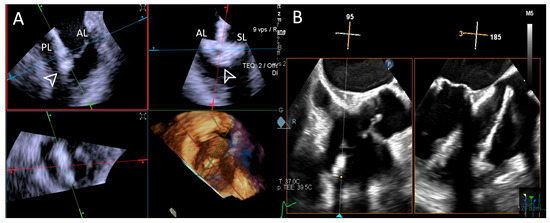

- Step number 3: steering and valve approach.

- Step number 4: ensuring perpendicularity and correct trajectory.